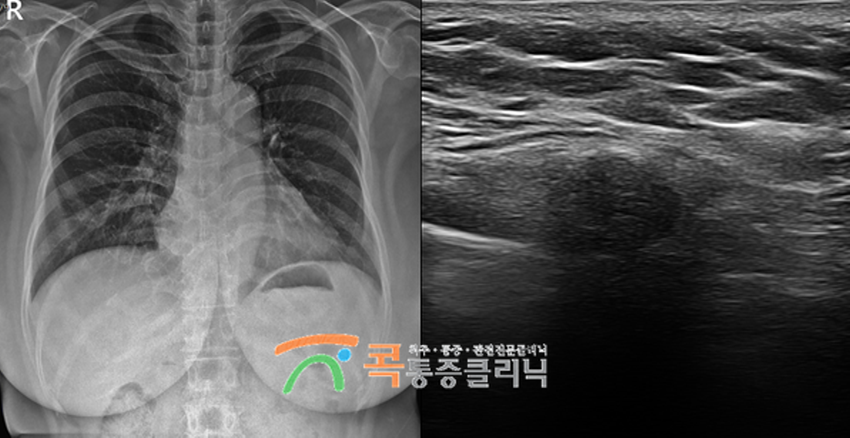

제가 대표원장으로 재직 중인 콕통증의학과에서는 초음파유도하 주사치료(SI치료)를 통해 늑간신경통을 치료합니다. 대학병원급 고해상도 초음파장비를 통해 염증이 일어난 병변 및 폐를 체크하면서 원인 부위에 직접 약물을 주입시키는 방법으로 90% 이상의 시술 정확도로 신뢰할 수 있습니다. 늑간신경 부위는 주요 기관인 폐와 인접해 있어 자칫 잘못된 시술은 기흉으로 이어질 수 있어 특별한 주의가 필요합니다.